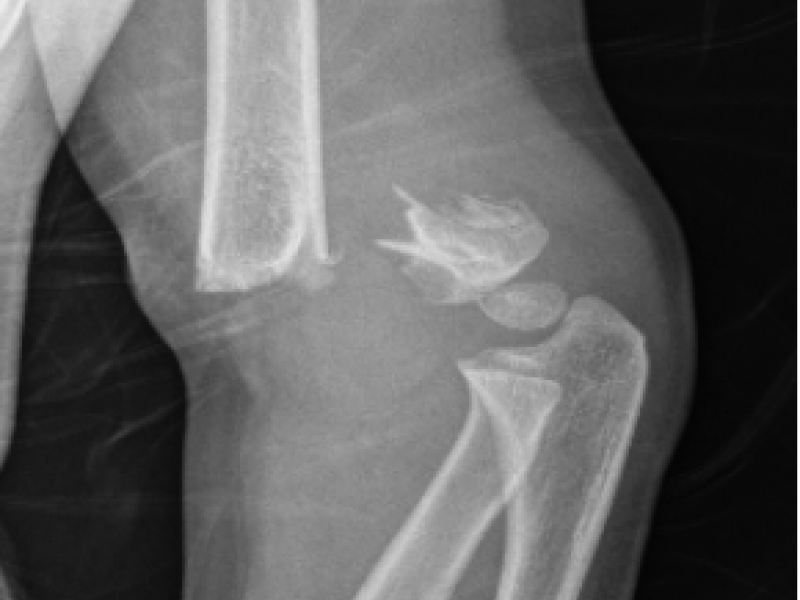

Back to Basics: Lunate vs Perilunate Dislocation

Back to Basics: Lunate vs Perilunate Dislocation By: Angela